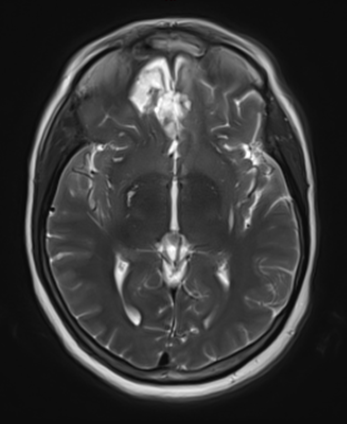

Figure 1b – Postoperative MRI demonstrating a complete resection without residual enhancement.

She was started on high-dose steroid and antiseizure prophylactic medicine. Surgical intervention was offered for mass effect, symptomatic relief, neurologic preservation, and histopathologic diagnosis. Dr. Gaudin performed a bifrontal craniotomy with complete resection of neoplasm through an interhemispheric and subfrontal approach. Postoperative imaging demonstrated a gross total resection without residual tumor and resolution of mass effect (Figure 1b and 2b). Intraoperative pathology was consistent with meningioma, WHO grade 1. She recovered very well, and was discharged home on postoperative day 3. On her follow-up outpatient visit, her preoperative symptoms had fully resolved, and her olfactory sense was maintained.

Figure 2b – Postoperative MRI demonstrating resolution of mass effect.